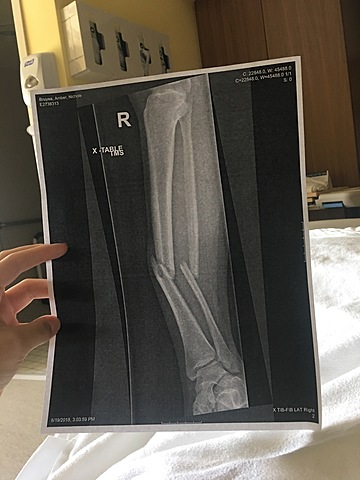

We as a team went to TNT gymnastics and they were doing skills and I already had those skills so I wanted to try some new ones. I was trying a new skills and I didn't land it and broke my right leg.

We went in for a check up on how my leg was doing and by the x-ray my leg had gotten worse. The cast wasn't doing my leg any good so the doctor said I had no choice but to get surgery.